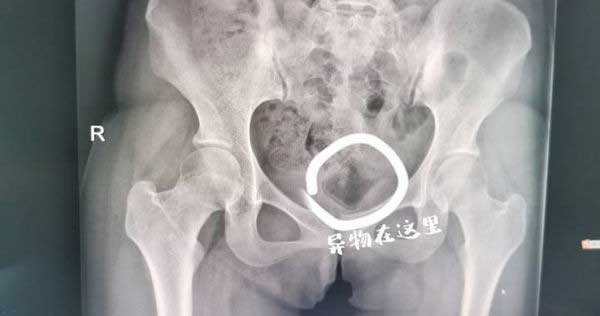

Bác sĩ đã kiểm tra và phát hiện có dị vật nằm sâu trong âm đạo của Tiểu Dương, vật thể nhẵn và không thể lấy ra bằng các dụng cụ y tế thông thường. Bác sĩ Cao Kiến Tùng cho biết, dị vật lưu lại trong cơ thể bệnh nhân khá lâu nhưng rất may vị trí không sâu.

Nhờ công nghệ sóng siêu âm hỗ trợ, sau nhiều lần thăm dò, cuối cùng dị vật trong cơ thể Tiểu Dương đã được đưa ra ngoài bằng kẹp phẫu thuật. Hóa ra, dị vật cặp đôi nhét vào 'vùng kín' trong lúc ân ái là nắp đậy mỹ phẩm có chiều dài 5cm và chiều rộng 3cm.